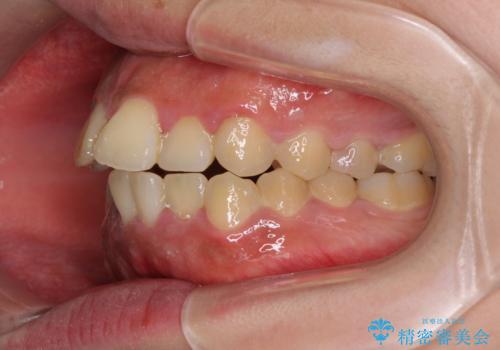

- 口元の突出感と上下前歯のでこぼこを気にして来院された患者様です。

上下前歯部叢生のスペース獲得のため、上下顎左右小臼歯各1歯(計4本)を抜歯して、矯正治療を行うこととしました。

口腔内の清掃性に問題があり、虫歯のリスクが極めて高かったため、短期で治療を終えることを最優先に治療を進めました。